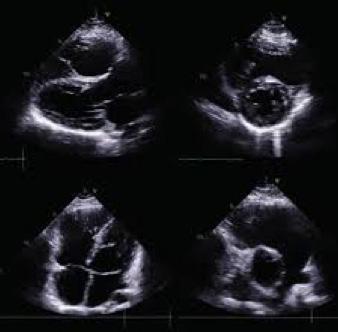

La tétralogie de Fallot se caractérise par quatre anomalies distinctes, comme ÉtienneLouis Fallot, anatomopathologiste, les avait observées lors d’autopsies. En réalité, deux de ces anomalies suffisent à expliquer la physiopathologie de cette malformation, les deux autres n’étant que des conséquences. Cette introduction vise à offrir un aperçu des caractéristiques cliniques, des défis diagnostiques et des approches thérapeutiques actuelles de cette pathologie (figure 1 ).

Anomalies anatomiques de la tétralogie de Fallot :

■ Rétrécissement de l’artère pulmonaire.

■ Hypertrophie du ventricule droit, qui compense la pression exercée par le rétrécissement de l’artère pulmonaire.

■ Communication interventriculaire entre les ventricules droit et gauche.

■ Malposition de l’aorte à droite, chevauchant le septum interventriculaire. Ce déplacement partiel au-dessus du ventricule droit résulte du défaut d’alignement à l’origine de la communication interventriculaire.

Cœur normal Tétralogie de Fallot

Dextroposition de l’aorte Sténose pulmonaire

Communication inter-ventriculaire

Hypertrophie ventriculaire droite

Figure 1 : Différence entre un cœur normal et un cœur ayant une malformation appelé la tétralogie de Fallot.

Anomalies principales :

■ Sténose (rétrécissement) de la voie d’éjection du ventricule droit : Cette sténose peut se situer au niveau de l’infundibulum pulmonaire, de l’anneau pulmonaire ou du tronc de l’artère pulmonaire (avant la bifurcation en deux artères pulmonaires). Le rétrécissement peut être localisé ou prédominer sur une de ces trois parties dans les formes mineures. En revanche, dans les formes sévères, il peut s’étendre à l’artère pulmonaire, y compris aux branches droite ou gauche.

■ Communication interventriculaire (CIV) : Cette communication se situe près de l’origine des gros vaisseaux, notamment de l’aorte. Elle résulte d’un mauvais alignement entre l’aorte et la portion musculaire du septum interventriculaire.

Ces caractéristiques anatomiques et physiopathologiques permettent de comprendre la complexité et la gravité de la tétralogie de Fallot, nécessitant une prise en charge médicale spécialisée.